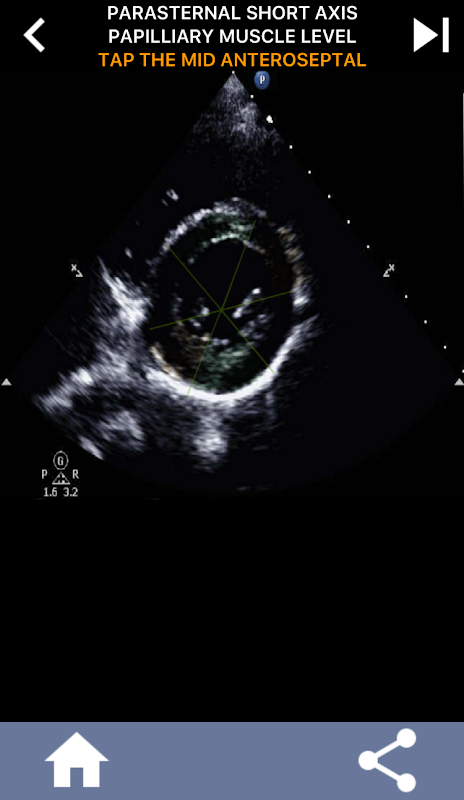

วิธีการใช้ภาพแบบทดสอบเพื่อเรียนรู้ส่วนหัวใจ AHA: Echocardiography

การทำความเข้าใจเกี่ยวกับส่วนของหัวใจ AHA (American Heart Association) มีความสำคัญสูงสุดสำหรับนักตรวจคลื่นเสียงหัวใจในการสื่อสารกับแพทย์โรคหัวใจที่เขียนรายงานได้อย่างมีประสิทธิภาพ เมื่อทราบบริเวณทางกายวิภาคเฉพาะและส่วนที่สอดคล้องกัน ช่างภาพสามารถอธิบายและสื่อสารความผิดปกติหรือสิ่งที่ค้นพบได้อย่างถูกต้อง ทำให้มั่นใจได้ว่าการสื่อสารที่ชัดเจนและรัดกุมระหว่างผู้เชี่ยวชาญทั้งสอง

ความเข้าใจนี้มีความสำคัญอย่างยิ่งเมื่อแพทย์โรคหัวใจพยายามค้นหาตำแหน่งที่แม่นยำของปัญหา หรือเมื่อแพทย์ที่โทรเรียกพบปัญหาภายในพื้นที่หนึ่งๆ กระตุ้นให้ผู้ตรวจวิเคราะห์ด้วยคลื่นเสียงแสดงส่วนที่เกี่ยวข้องอย่างแม่นยำ เช่น ผนังกึ่งกลางด้านล่าง ดังนั้น การมีความเข้าใจที่ครอบคลุมในส่วนของหัวใจ AHA จึงเป็นชุดทักษะที่จำเป็น

แอปนี้จะทดสอบความรู้ของคุณโดยใช้ภาพสะท้อนจริง ซึ่งฉันมักจะพบว่าเป็นวิธีการสอนที่ดีที่สุด